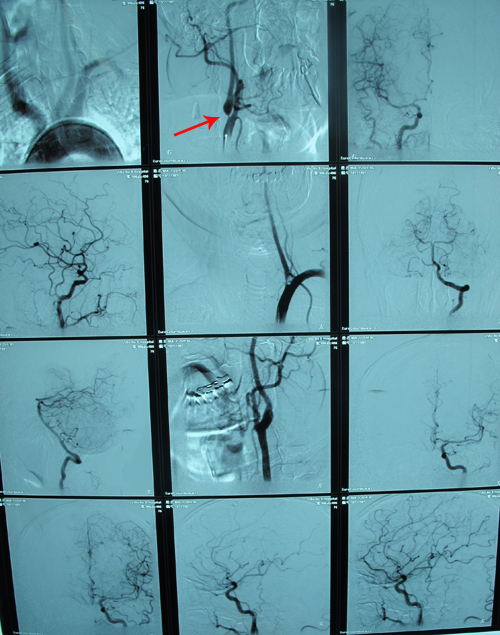

全脑血管造影:右颈内动脉、右椎动脉起始部分别狭窄95%,90%,右椎动脉颅内段未显影。

颈部血管超声:双侧颈动脉硬化斑块形成,右侧颈动脉狭窄,右侧椎动脉狭窄供血不足并高阻。